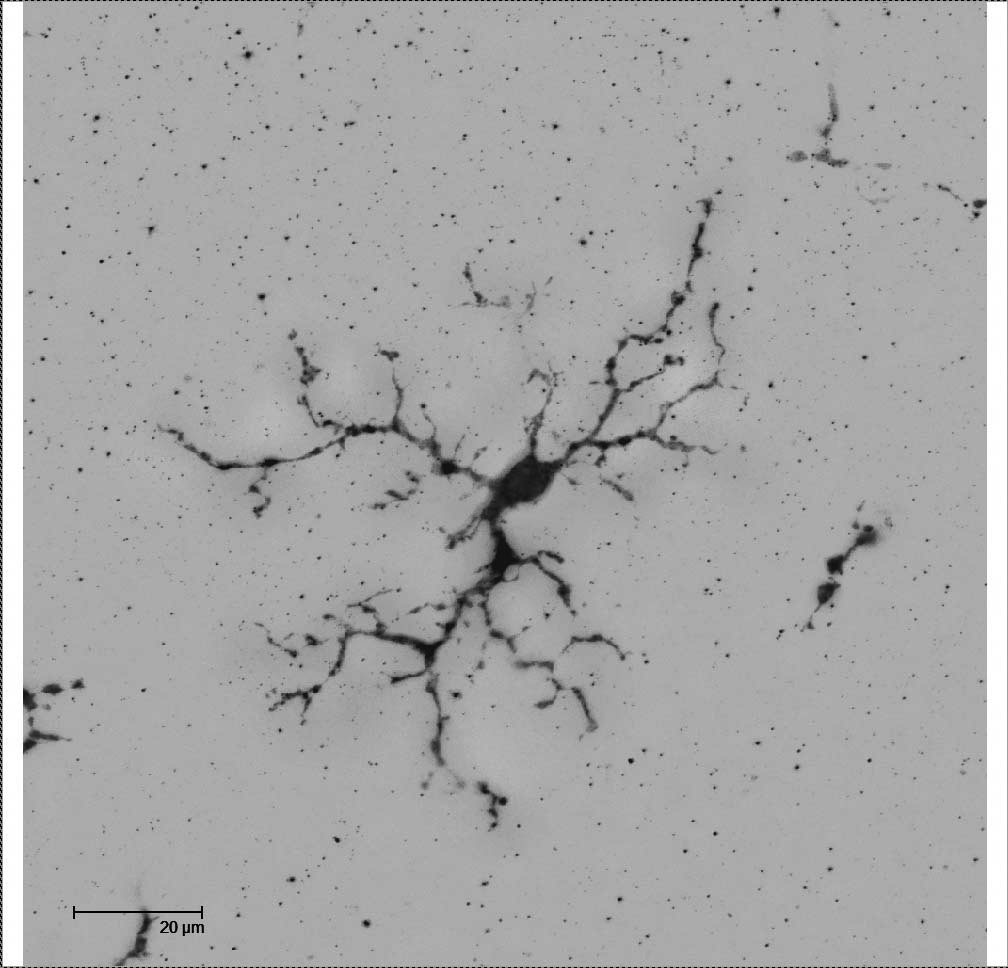

MicrogliaMouse

Glial cells MicrogliaRat OX42

Glial cells. MicrogliaRat SD Ox42

MicrogliaRat. Iba1